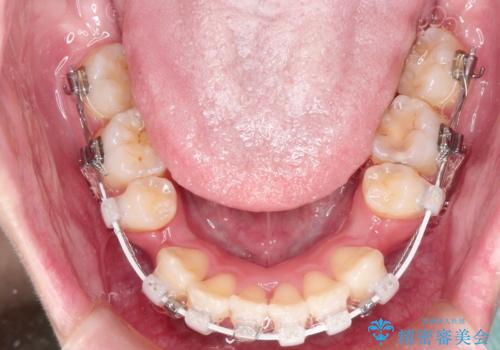

- 矯正装置

- ハーフリンガル

- 前歯が出ているため口が閉じにくく、横顔が気になるとのことで来院された患者様です。。

上下の前歯が前方に傾斜しており、口唇の突出感がありました。

上下左右の前から4番目の歯を抜歯して、上下の前歯を後方に移動させる計画としました。